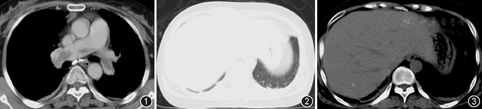

患者女,50岁,因"下肢肿胀疼痛半个月,晕厥、气促4 d,胸痛1 d"于2015年8月30日入院。患者2015年8月11日于外院行"清宫术"后阴道流血,给予"酚磺乙胺"静脉滴注7 d,用药期间右下肢逐渐出现肿胀、疼痛,诊断为"风湿病"并给予消炎镇痛治疗后疼痛减轻,但肿胀无改善。3 d前患者突发晕厥,约10 s后意识恢复,自觉气促、胸闷。下肢彩色多普勒超声检查示:右侧股总、股浅、腘静脉、胫后近段静脉血栓(完全性),诊断"下肢静脉栓塞" 。转至上级医院给予抗凝治疗伊诺肝素钠0.4 ml皮下注射,12 h/次。患者凌晨自觉右侧胸痛,行CT肺动脉造影(CTPA)检查示:双肺动脉主干栓塞,骑跨型肺栓塞,未见明显肺梗死(图1图2图3),为进一步诊治转入我院。既往史:甲状腺功能亢进病史3年,规律服用"甲硫咪唑"治疗,半年前曾经出现右小腿疼痛、稍肿胀自行好转无就医。否认脑血管意外、高血压病史,平素血压约120/70 mmHg(1 mmHg=0.133 kPa),近期无腰椎、眼部手术史,否认服用避孕药、雌孕激素及糖皮质激素史。家族史:母亲及2位妹妹均有下肢深静脉栓塞病史。个人史:无特殊。入院体检:体温36.5 ℃,脉搏80次/min,呼吸24次/min,血压119/71 mmHg,SpO2 93%(吸氧3 L/min),体重61 kg。口唇无发绀,双肺呼吸音清,未闻及干湿性啰音。腹平软,无压痛、反跳痛,肝脾不大,肝肾区无叩击痛。右下肢肿胀,皮温稍高,肌力正常,无感觉功能减退。入院相关检查:血气分析:pH值为7.41,吸氧浓度(FiO2) 30%,PaO2为94.3 mmHg,PaCO2为38.3 mmHg,肺泡动脉氧分压差[P(A-a)O2] 67.9 mmHg;凝血功能:D-二聚体(ELISA法)>10 000 ng/ml,凝血酶原时间 (PT) 14.7 s ,活化部分凝血活酶时间 (APTT) 44.2 s,凝血酶时间(TT) 15.4 s,纤维蛋白原3.30 g/L;心肌损伤相关检查:谷草转氨酶:41.6 U/L,肌酸激酶:15.4 U/L,肌酸激酶MB同工酶:12.0 U/L,乳酸脱氢酶:294.4 U/L,肌钙蛋白(CTnI)0.1 μg/L,肌红蛋白:7.5 μg/L;易栓症相关检查:蛋白S 11%,蛋白C 53%,抗凝血酶Ⅲ 65%。下肢深静脉彩色多普勒超声示:右股总静脉远端至小腿段完全性栓塞,伴丰富的侧支循环,右股总静脉近心端及大隐静脉未见异常团块。心电图未见明显异常(图4)。心脏彩色多普勒超声提示右心增大,三尖瓣反流(轻度),肺动脉高压(轻度),左心室收缩功能未见异常。入院后根据体重给予伊诺肝素钠0.6 ml,1次/12 h皮下注射,第2天患者气促较前加重。体检:呼吸急促,三凹征,呼吸27次/min,脉搏氧饱和度(SpO2)90%(吸氧4 L/min),血压103/62 mmHg。考虑病情较前加重,为避免病情恶化与家属充分沟通并签署同意书后,给予重组人组织纤维蛋白溶酶原激活剂(rt-PA)50 mg,2 h方案溶栓治疗[1]。溶栓过程顺利患者无出血、无不良反应。溶栓后患者气促、胸痛症状明显好转,体检:呼吸22次/min,SpO2 96%(吸氧2 L/min),血压113/71 mmHg。间隔2 h复查APTT减至60 s后给予续贯低分子量肝素(药物、剂量同前)抗凝治疗。溶栓后第2天无明显诱因出现左季肋区疼痛明显,深呼吸加重,腹部无压痛、反跳痛,复查血常规血红蛋白未见明显降低,急查血淀粉酶30 U/L,脂肪酶225 U/L,腹平片排除胃穿孔及肠梗阻。给予对症止痛治疗效果不明显。溶栓后第4天复查胸部CT造影对比溶栓前CT示:(1)双侧肺动脉主干血栓消失、右下肺基底段肺动脉栓塞较前明显改善;(2)左下肺外基底段肺梗死(图5图6图7);腹部增强CT提示:腹部未见异常。考虑溶栓后肺动脉内血栓分解脱落栓塞远端肺动脉,导致肺梗死。继续予以足量低分子量肝素抗凝、吸氧、止痛等对症支持治疗,症状逐渐减轻好转,继续治疗1周后下肢血栓较前减少,9月13日出院,出院给予口服利伐沙班15 mg,2次/d,连续服用3周后改为20 mg,1次/d。